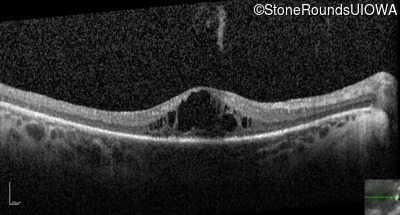

Optical Coherence Tomography - Right - 20/80 +2

Exemplar / OCT Stack